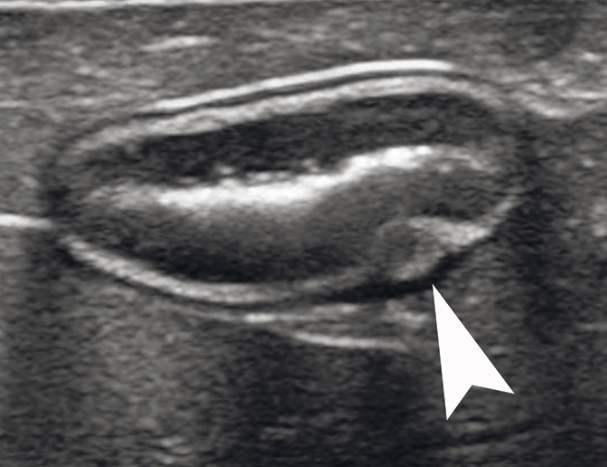

정상 고양이의 췌도 개구부 초음파 영상

초음파 진단시 참고 자료